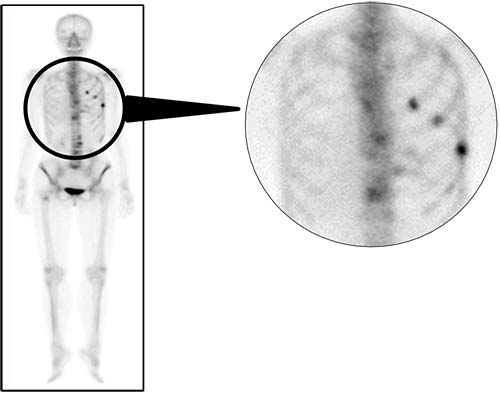

核医学検査(RI 検査)

放射性同位元素(Radio Isotope:RI )を用いた検査のことで、目的とする臓器や腫瘍に集まる薬にRIで目印を付けて投与し、放出される放射線(ガンマ線)を専用のカメラで計測します。 核医学検査はSPECT(スペクト)とPET(ペット)に分けられ、さらに心臓、脳、肺、骨、腫瘍など検査目的によって多くの検査に分けられます。

当院の核医学検査(PET検査、SPECT検査)は核医学専門技師の認定を受けた診療放射線技師を中心とし、放射性医薬品の管理や機器精度管理のもと撮影を担当しています。

●SPECT検査︓ Single photon emission computed tomography

・⾻シンチグラフィ

- ラジウム-223による去勢抵抗性前⽴腺がんの⾻転移治療